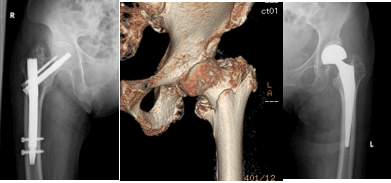

しかし、一概に股関節の骨折、大腿骨近位部骨折といっても様々なタイプの骨折があり、どのような骨折にどのような治療を行なうべきか、専門医の間でも、世界的に議論されてきましたが、我々秋田県股関節研究会が1000例以上の秋田県の方の骨折を詳細に分析した結果、秋田ならではの治療方針決定方法を開発しました(大腿骨近位部骨折のAkita分類-Kijima H, et al. Adv Orthop. 2014, SpringerPlus 2016など-)。

1. The reliability of classifications of proximal femoral fractures with 3-dimensional computed tomography: the new concept of comprehensive classification.

Kijima H, Yamada S, Konishi N, Kubota H, Tazawa H, Tani T, Suzuki N, Kamo K, Okudera Y, Sasaki K, Kawano T, Shimada Y.

Adv Orthop. 2014;2014:359689. doi: 10.1155/2014/359689. Epub 2014 Dec 25.

2. The choice of internal fixator for fractures around the femoral trochanter depends on area classification

Kijima H, Yamada S, Konishi N, Kubota H, Tazawa H, Tani T, Suzuki N, Kamo K, Okudera Y, Sasaki K, Kawano T, Miyakoshi N, Shimada Y

SpringerPlus2016 5:1512 (Impact Factor: 0.982)

6. A case of fracture-redislocation of the hip caused by a depressed fracture of the femoral head similar to a Hill-Sachs lesions.

Okudera Y, Kijima H, Yamada S, Konishi N, Kubota H, Tazawa H, Tani T, Suzuki N, Kamo K, Sasaki K, Kawano T, Miyakoshi N, Shimada Y

Case Rep Orthop. 2017.